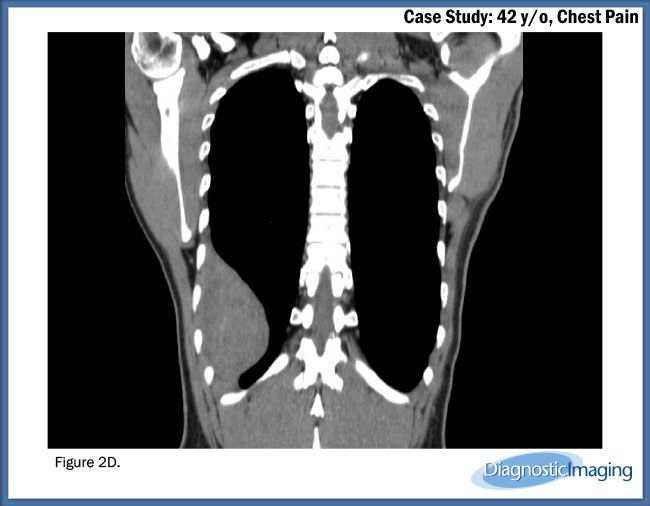

Case History: 42-year-old patient presented with chest pain.

Case History: A 42-year-old patient presented with chest pain.